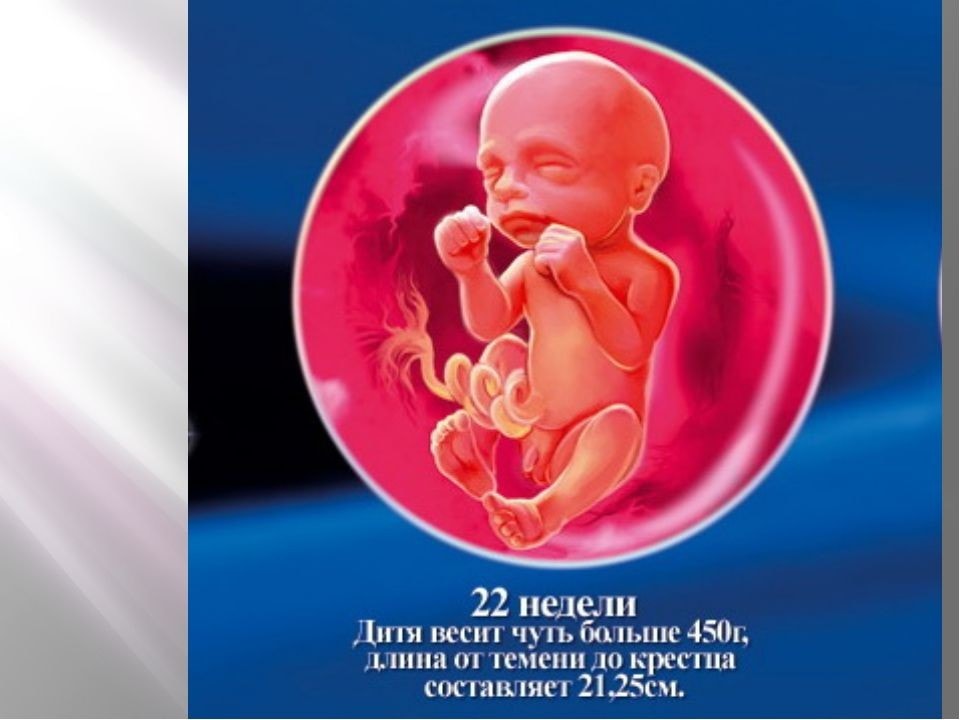

Какие изменения происходят с плодом на 22 неделе беременности?

На 22 неделе беременности плод продолжает развиваться и весит уже около 450 граммов. Его длина составляет примерно 27 см. Наблюдается активное формирование мозга и нервной системы, а также развитие мышц и костей. Появляются пальчики на ногах и руках, формируются пальцы. Органы слуха продолжают развиваться, а кожа покрывается слоем мягкого волосяного покрова.

Что происходит с плодом в 22 недели гестации

Вес ребенка составляет около 680-700 граммов, а рост порядка 22 см. Малыш активно обрастает жирком, идет развитие его костной и мышечной ткани, совершенствуются внутренние органы.